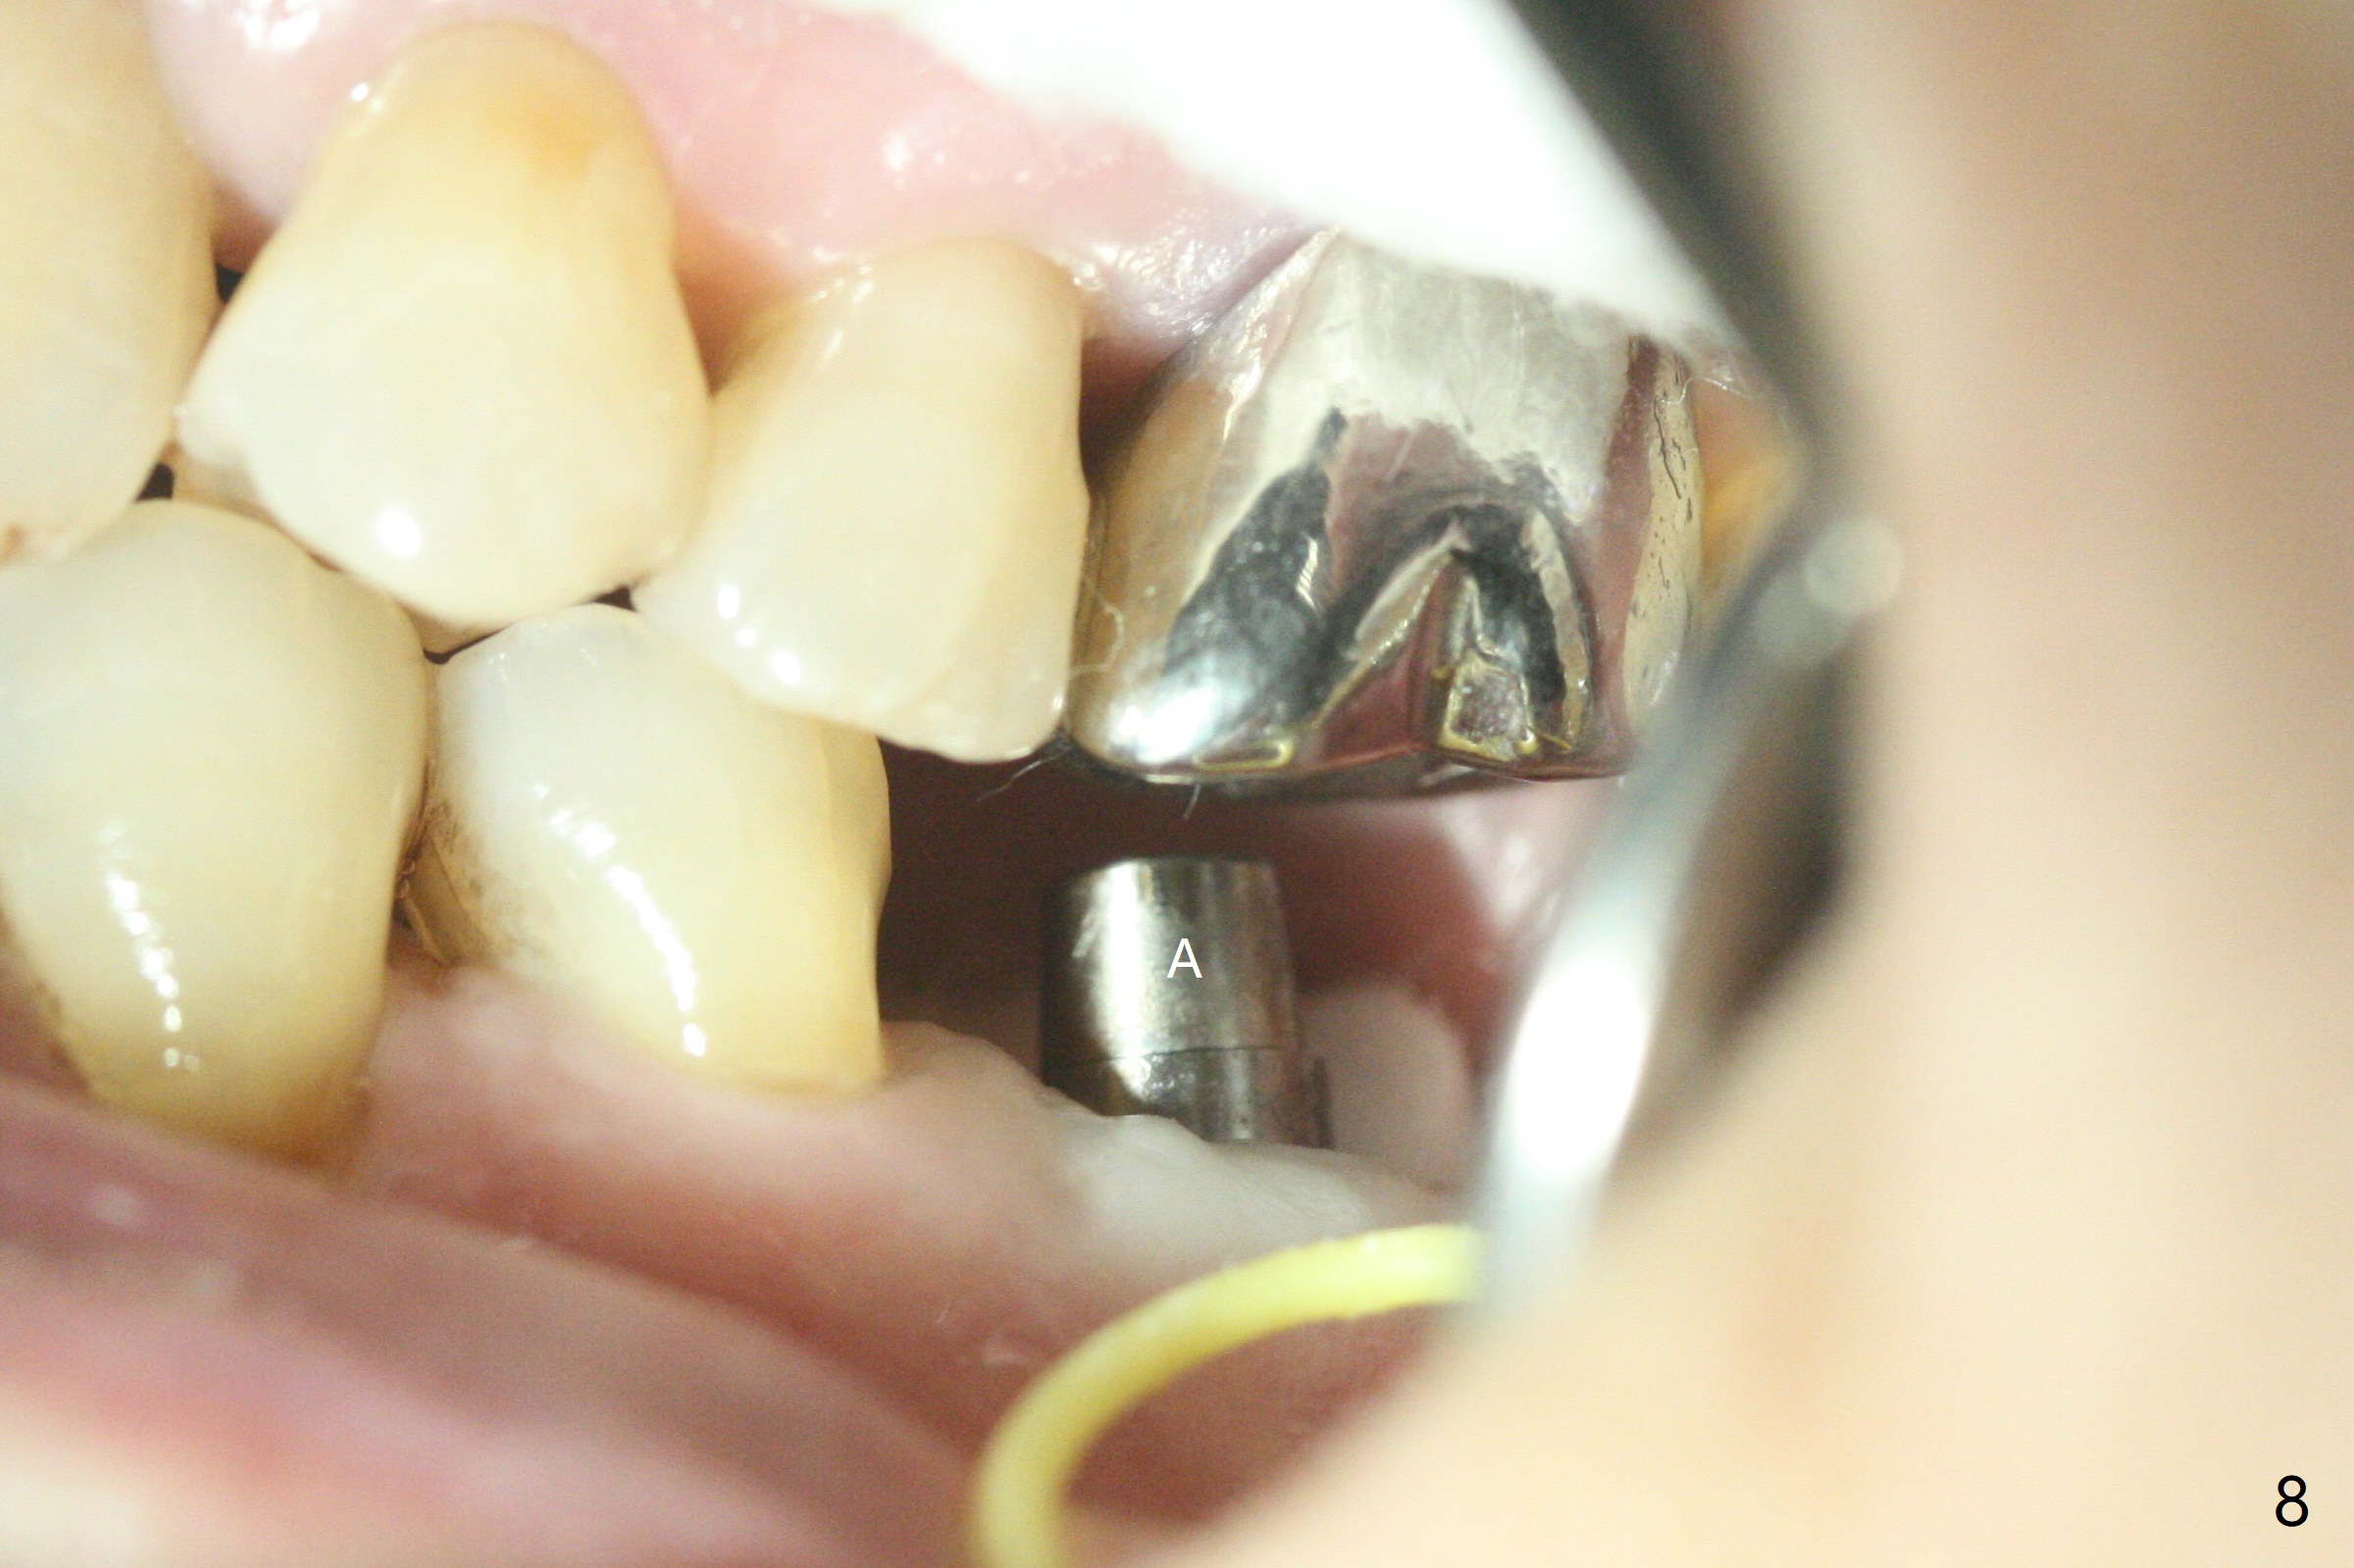

Apical 3 mm Underdrill Post Cortical Drill M

Following light use of 4 mm tissue punch, a buccal incision is made and raised. After 4x8.5 mm drill with 10.5 mm offset at #19, 4.5 mm cortical drill is used for 2/3 length to take care of the thick dense lingual plate (overprep). The remaining apical 3 mm osteotomy is underdrill (3.5 mm). After try-in of a 4.5x14 mm tissue-level dummy implant, a same-sized definitive one obtains 35 Ncm torque (Fig.1). Following 3-4 more turns, the torque reaches 45 Ncm (Fig.2) with the distal thread covered (<) and autogenous bone graft placed in the distal defect (*). A 4x3 mm unipost is placed to keep periodontal dressing in place. Clinically the implant is placed within bone boundary buccolingually. The new implant seems necessary considering short (Fig.2 S) and probably resorbed (Fig.1 R) roots of the premolars. In fact the short abutment keeps the mesiolingual portion of periodontal dressing for 2 weeks; since local hygiene is suboptimal, the healing screw is placed after abutment and dressing removal (Fig.3).